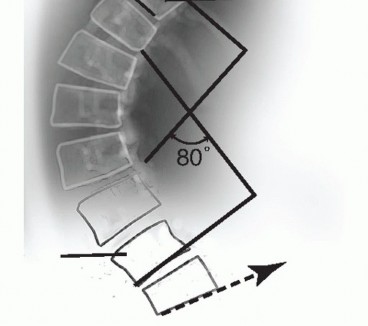

Standing lateral radiographs on 36-inch cassettes characterize the spinal deformity by Regional lordosis and kyphosis (FIG 6)

Sagittal balance: the relationship between the C7 plumb line and center of S1 on lateral views (FIG 7)

*FIG 6 • Regional lordosis and kyphosis are measured on the standing lateral radiograph. Typically, the vertebral endplates are used as **

*FIG 6 • Regional lordosis and kyphosis are measured on the standing lateral radiograph. Typically, the vertebral endplates are used as **

* **FIG 7 • Sagittal balance is evaluated on the standing lateral radiograph. It is measured as the anterior (positive) or posterior (negative) distance between the C7 plumb line and the center of the L5-S1 disc space.**